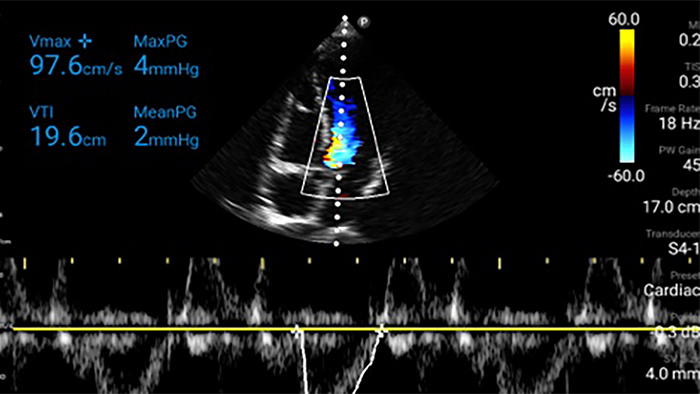

Lumify handheld ultrasound offers images that enhance diagnostic confidence.

See more when it counts

Lumify can help you make real-time decisions with more confidence, from assessment to recovery. Reveal the subtle details of an image, uncover enriched tissue definition with multiple angles and much more.